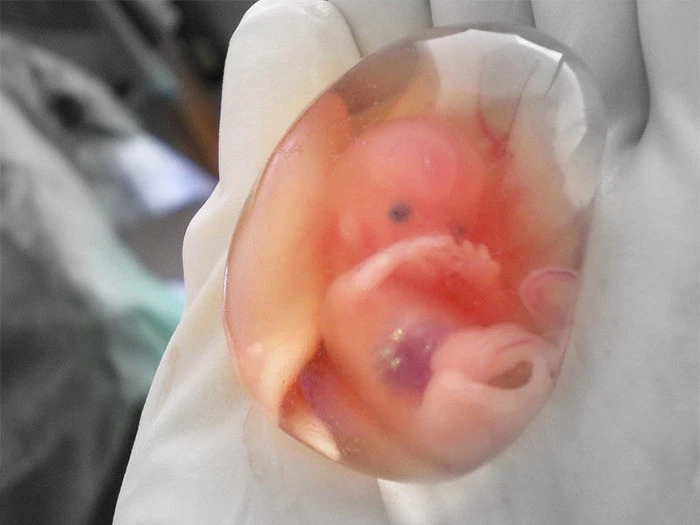

3. «От трети до половины всех оплодотворенных яйцеклеток не становятся жизнеспособной беременностью. Вместо этого они покидают тело под видом «обильной менструации». Большинство женщин даже не подозревают, что у них случился выкидыш».

8. «Женщины появляются на свет сразу со всеми яйцеклетками, которые они выпустят из яичников за свою жизнь. Следовательно, беременная женщина, вынашивающая ребенка женского пола, также вынашивает яйцеклетки, которые станут ее внуками».

22. «Если беременная женщина пострадала, стволовые клетки из ее матки переходят к поврежденным органам и восстанавливают их, чтобы защитить ребенка».

23. «Люди — вторичноротые. То есть первое, что развивается в эмбрионе, — это отверстие, которое в конечном итоге станет анусом. Значит, в какой-то момент ты был просто задницей».